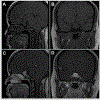

Figures